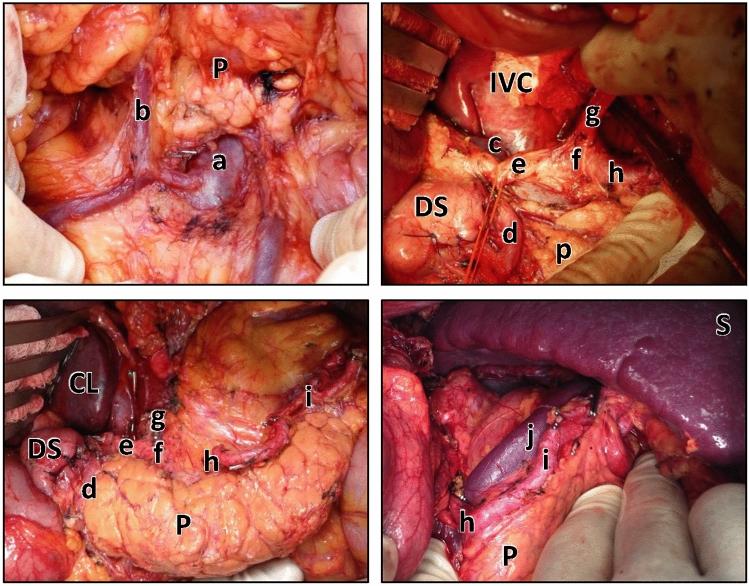

The operative steps for D1+ and D2 gastrectomy have been previously described in the literature and ADDICT trial manual. Two researchers also performed fieldwork in the UK and Japan to document key operative steps through photographs and semi-structured interviews with expert surgeons. This provided the steps that were used as the framework for the SQA tool. Sixty-two photographic cases from the ADDICT Trial were rated by three independent surgeons. Generalizability (G) theory determined inter-rater reliability. D-studies examined the effect of varying the number of assessors and photographic series they rated. Chi-square assessed intra-rater reliability, comparing how the individual assessor's responses corresponded to their global rating for extent of lymphadenectomy.

The tool comprised 20 items, including 19 anatomical landmarks and a global rating score. Overall reliability had G-coefficient of 0.557. Internal consistency was measured with a Cronbach's alpha score of 0.869 and Chi-square confirmed intra-rater reliability for each assessor as < 0.05.

A photographic surgical quality assurance tool is presented for gastrectomy. Using this tool, the assessor can reliably determine not only the quality but also the extent of the lymphadenectomy performed based on remaining anatomy rather than the excised specimen.